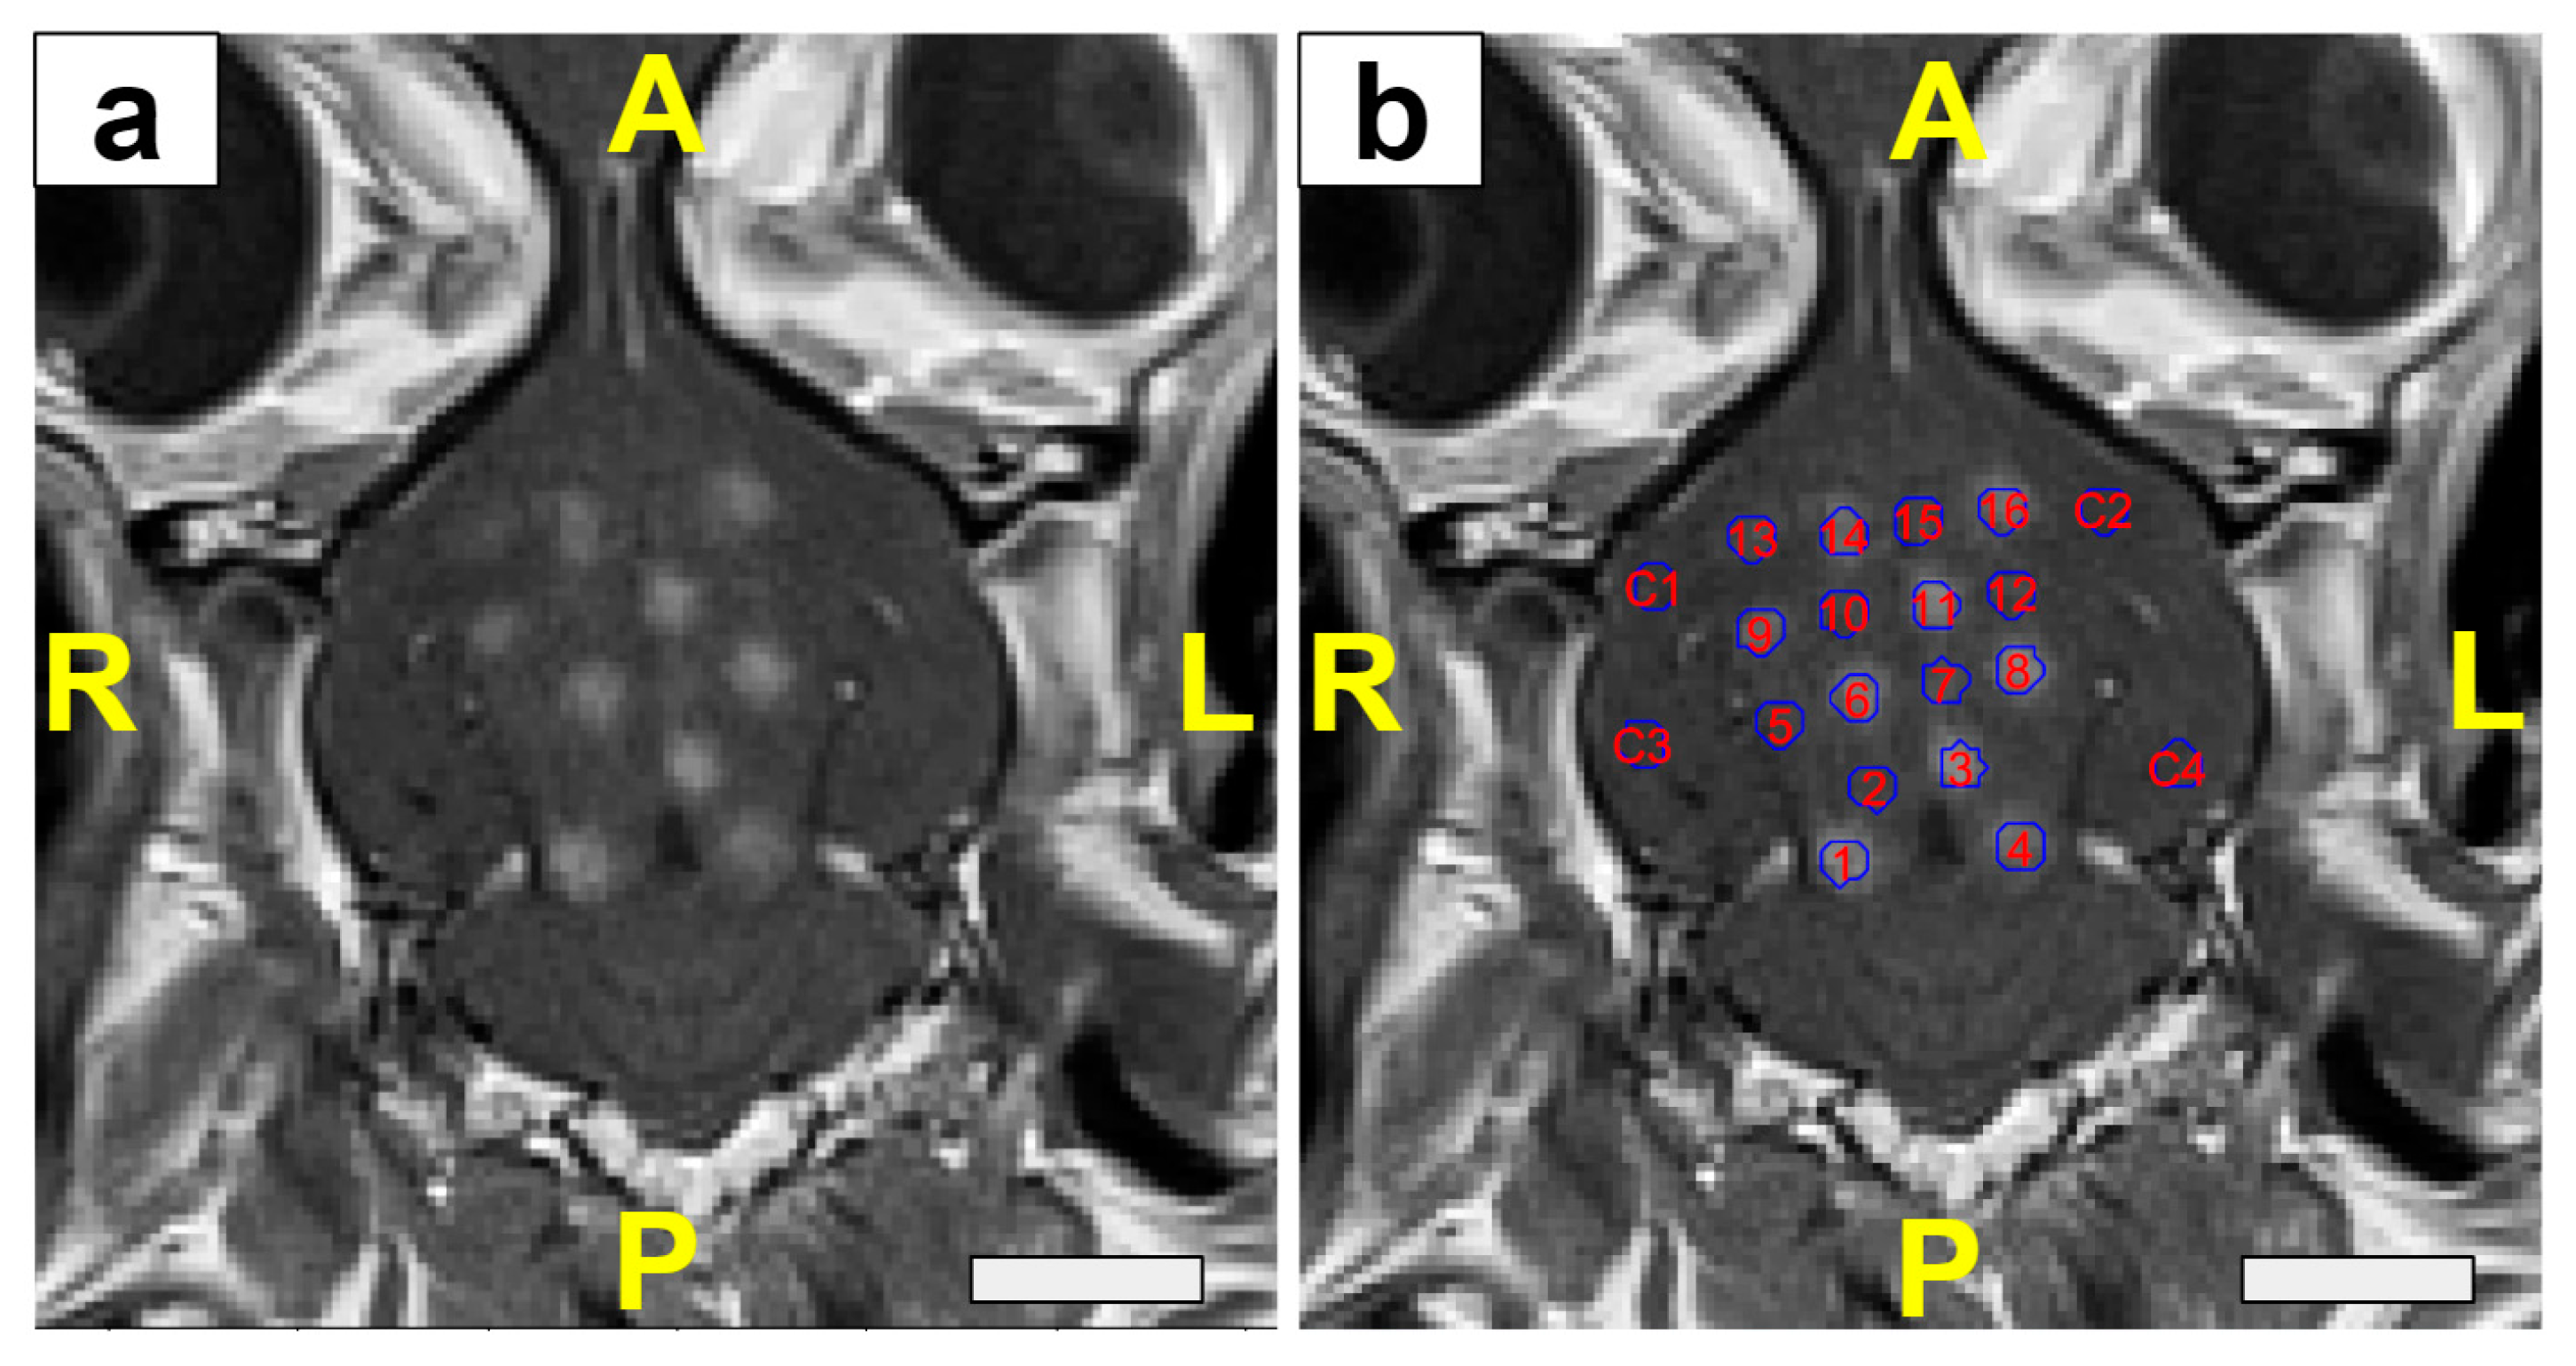

2.5. MRI and Quantification